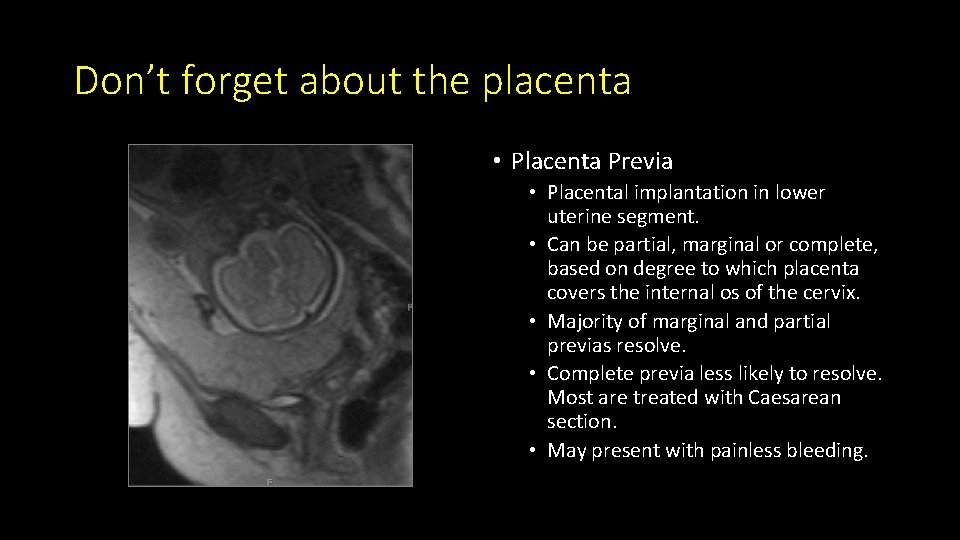

Don’t forget about the placenta • Placenta Previa • Placental implantation in lower uterine segment. • Can be partial, marginal or complete, based on degree to which placenta covers the internal os of the cervix. • Majority of marginal and partial previas resolve. • Complete previa less likely to resolve. Most are treated with Caesarean section. • May present with painless bleeding.